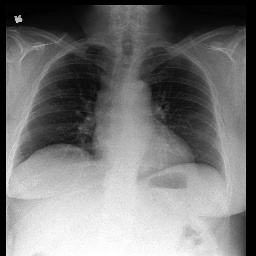

X-ray Medical Report. Figure 5 illustrates a side-by-side comparison of X-ray images alongside their respective ground truths and the reports generated by our model. It is clear that our method is capable of producing reports that closely align with the ground truth, with only minor discrepancies highlighted in mismatching terms but the overall performance of our framework on the MIMIC-CXR dataset is promising.